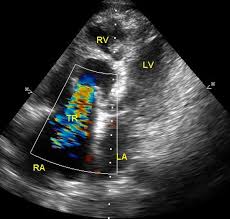

Рис.5. Візуалізація аневризми лівого шлуночка за даними ехокардіографії.